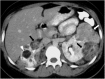

Hamartomas are tumours composed of mesenchymal tissues such as cartilage, fat, connective tissue and smooth muscle and can be found in virtually any organ system. These masses commonly develop sporadically, but are also seen in certain syndromes such as tuberous sclerosis or Carney triad. While their imaging appearance varies depending on the organ they arise from, findings are usually unique and a diagnosis can be confidently made. Radiologists must be aware of the clinical and imaging presentations of these lesions with the particular goal of avoiding unnecessary studies or invasive procedures. Furthermore, knowledge of common syndromic entities is crucial, as the radiologist may be the first to suggest the diagnosis.